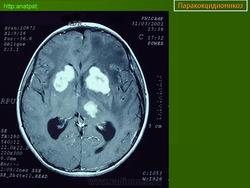

ГМ. Паракокцидиомикоз. +

Паракокцидиомикоз.

Множественные "узловые образования" имитирующие метастазы.